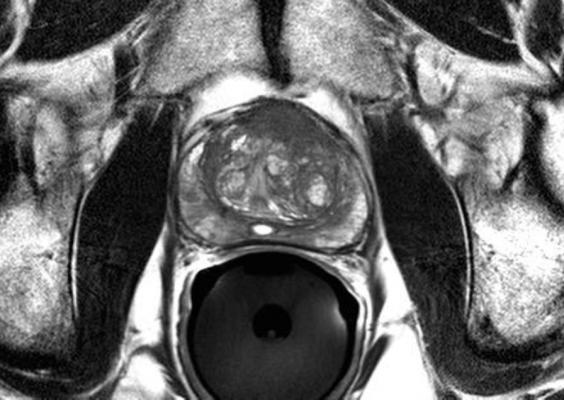

Brachytherapy is a type of radiation therapy (RT) where radioactive seed implants are inserted directly into a patient’s tissue to deliver treatment to the tumor while limiting radiation exposure for surrounding tissue.

Patients were randomized to one of two treatment arms, where 292 patients received brachytherapy alone (the B group) and 287 patients received 45 Gy partial EBT to the pelvic area in addition to brachytherapy (the EBT+B group). Brachytherapy treatment included the use of I-125 or Pd-103 (radioactive Iodine-125 or Palladium-103), prescribed to 110 Gy or 100 Gy respective boost dose for the patients who received brachytherapy plus EBT, and 145 Gy or 125 Gy respective dose for the patients who received brachytherapy alone. EBT was delivered by either intensity-modulated RT or three-dimensional conventional RT.